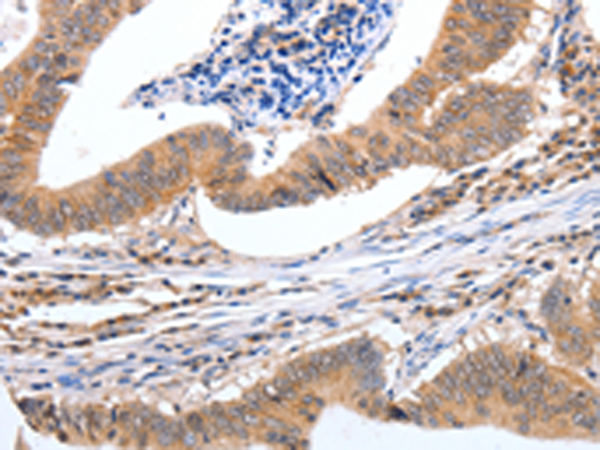

分类: 科研抗体货号: P07512别名: MEK3; MKK3; MAPKK3; PRKMK3; SAPKK2; SAPKK-2应用: WB,IHC反应种属: Human, Mouse